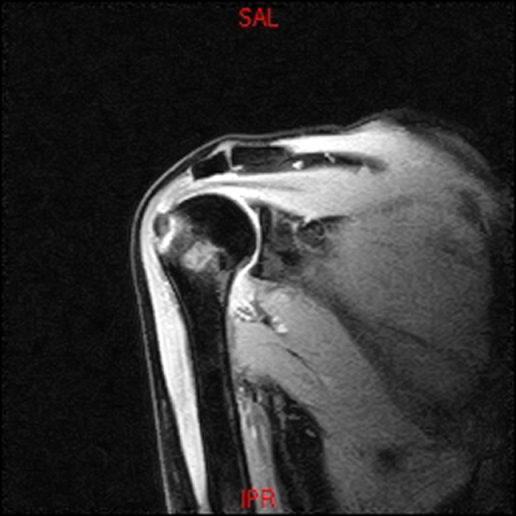

• Resonancia PATOLÓGICA DE HOMBRO - FRACTURA TROQUITER -  COR T1

• Resonancia PATOLÓGICA DE HOMBRO - FRACTURA TROQUITER Y EDEMA OSEO -  COR T2 WF

• Resonancia NORMAL HOMBRO COR T2 WF

• Resonancia NORMAL HOMBRO COR T1